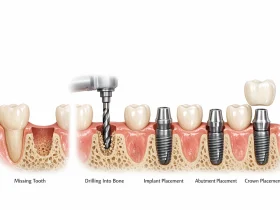

پروتز ثابت

پروتز ثابت نوعی از پروتز است که به صورت دائمی روی دندانها یا ایمپلنتها قرار میگیرد و بیمار نمیتواند آن را از دهان خارج کند. روکش دندان و بریج از جمله نمونههای رایج پروتز ثابت هستند. این نوع پروتز به دلیل ثبات بالا و شباهت زیاد به دندان طبیعی، در بسیاری از موارد گزینهای مناسب برای جایگزینی دندانهای از دست رفته محسوب میشود.